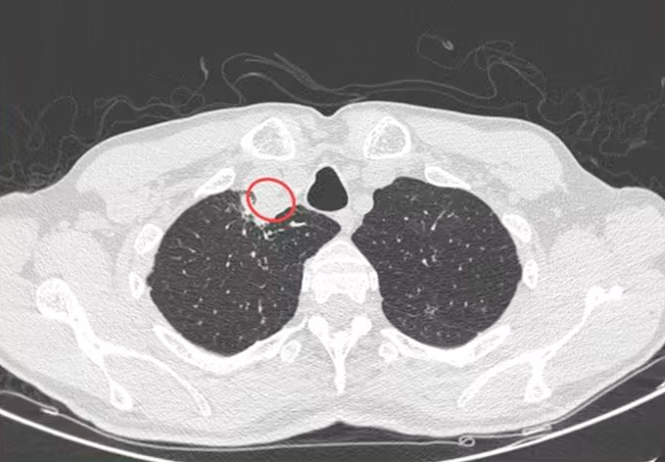

经过CT扫描,医生发现该男子脖子上出现了一个气管旁脓肿,阻塞了他的部分气道,液体检测结果震惊了所有医生:该男子感染了名为紫韧革菌的真菌,这也是导致植物银叶病的真菌。